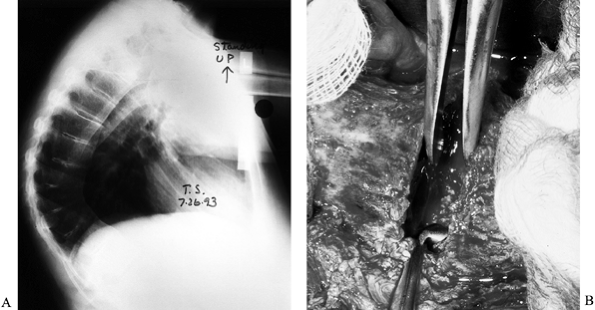

This syndrome is frequently seen after posterior distraction

instrumentation in the lumbar spine, especially if the instrumentation

approaches L-5 or the sacrum without supplemental anterior support (Fig. 161.8).

![]() |

|

Figure 161.8. A:

This 14-year-old boy has Gauché’s disease with collapse of T-12, L-2, and L-5, with kyphosis and back pain. He has been treated for several years with an orthosis. B: Six months after posterior fusion and instrumentation to the sacrum, the lumbar lordosis was minus 13°. He had difficulty maintaining an upright posture (flatback syndrome). C: After anterior/posterior osteotomies, fusion, and instrumentation, the sagittal alignment is much improved. |